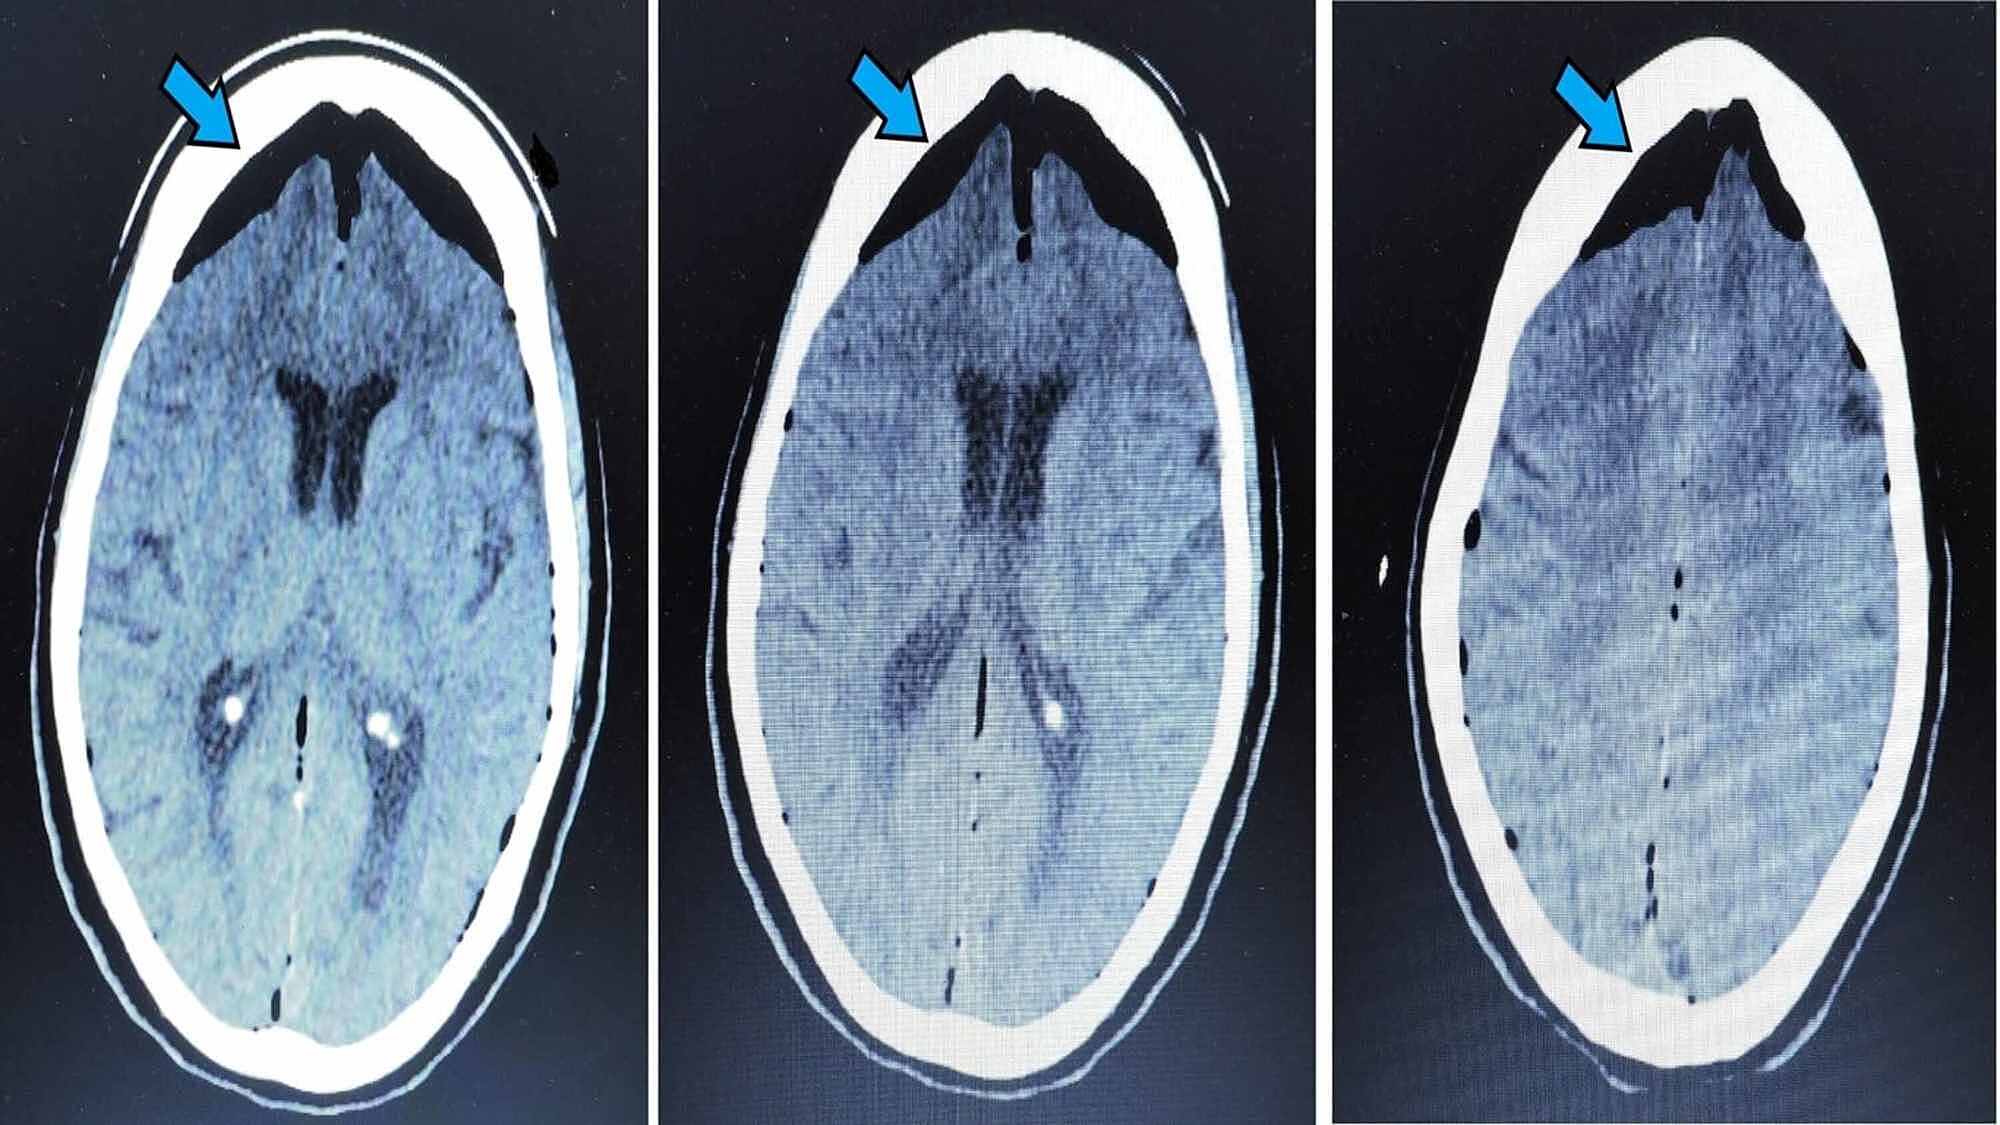

Pneumocephalus After Surgical Evacuation Of Chronic Subdural Hematoma Is It A Serious Complication Ihab Z Asian J Neurosurg